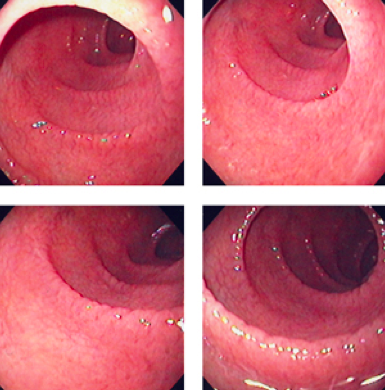

What is going on here?

What might this be?